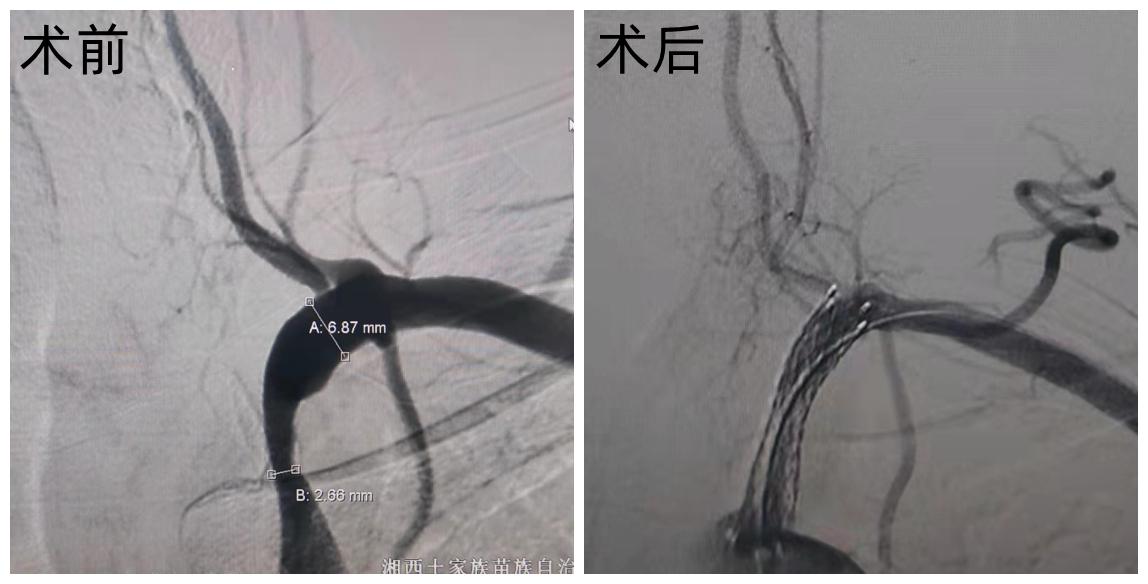

术后可见狭窄已经明显改善 锁骨下动脉盗血是指在锁骨下动脉或头臂干的椎动脉起始处的近心段,有部分或完全闭塞性损害,由于虹吸作用(盗血),引起患侧椎动脉中的血流逆行,进入患侧锁骨下动脉的远心端,导致椎基动脉缺血性发作和上肢缺血性的症候,从而出现眩晕、眼花、走路不稳,有些患者会出现头痛、头枕部疼痛或听力减退等,严重者会引起偏瘫、失语、上肢运动后意识丧失等。

术后可见狭窄已经明显改善